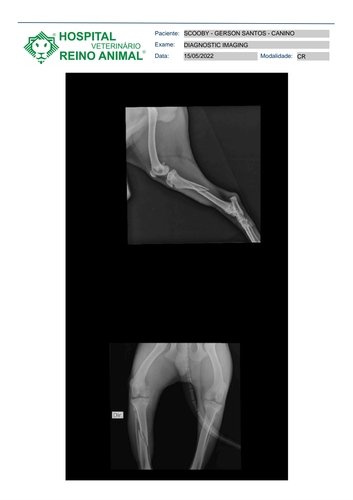

Por um inesperado acidente, meu cachorro teve uma fratura na TÍBIA, osso da perna traseira direita, ocorrido por um pouso desajeitado no chão após ter dado um salto bem alto para tentar pegar um petisco na mão da minha irmã!

O levei ao hospital veterinário, já fizeram os primeiros socorros e o laudo médico constou Fratura na TÍBIA, que para tratar precisará fazer uma cirurgia, colar placa e pinos!

Abaixo tem as imagens do raiox do fratura e do animal! e os custos dos hospital!